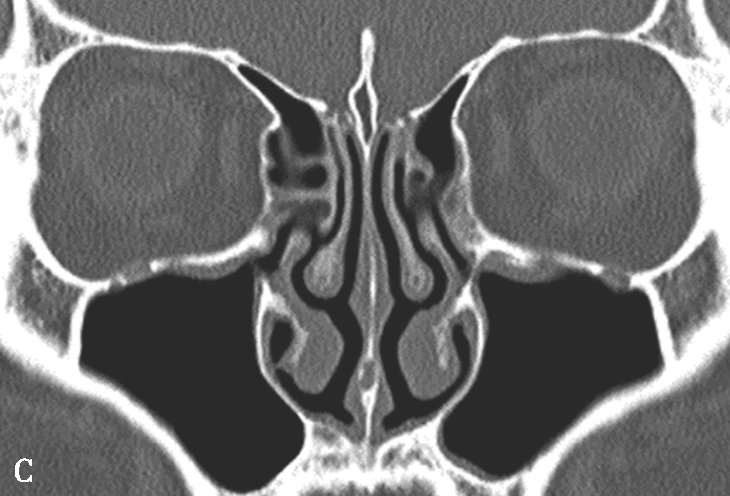

筛骨迷路过度气化时中鼻甲也可气化,发生在中鼻甲前部时称为甲泡,发生于中部时称为筛甲气房。中鼻甲气化可使中鼻道狭窄,可能影响半月裂的引流(图1-3-3)。

图1-3-3 中鼻甲解剖变异

A.双中鼻甲气化;B.左中鼻甲反曲;C.左中鼻甲发育小